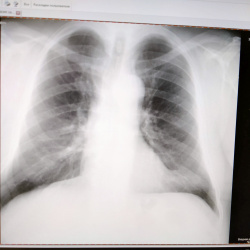

Здравствуйте, женщина 59 лет, профосмотр, не нравится левый корень, расширен? Или это из-за ротации? Если нет то направить на КТ или это норма?

Здравствуйте, мужчина 62 года, профосмотр. За счёт чего может быть эта округлая тень? Стоит направить на КТ или нет?